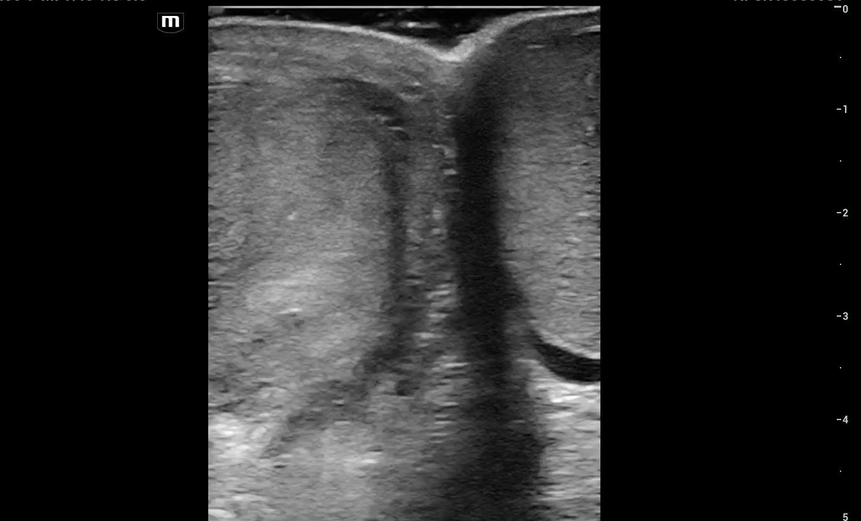

This is what we see:

Right Testicle is shown above.

• Notice how the echotexture of the testicle is not homogenous all the way through, which should catch your eye as a potential abnormal finding.

• It is important to also note that the anechoic area to the R of the screen can be hematocele, abscess (less likely), varicocele, or hydrocele. Clinical context is very important to making the correct diagnosis with ultrasound.